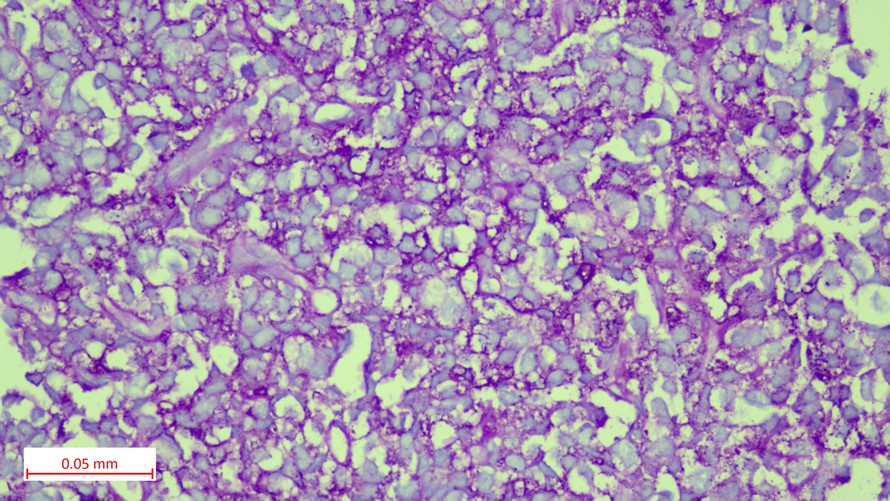

Histopathological findings

• Tumor cells showed a round to oval nucleus with inconspicuous nucleoli, scant eosinophilic to clear cytoplasm (PAS positive) and indistinct cytoplasmic borders. In few areas, tumor cells showed hyperchromatic angulated nuclei